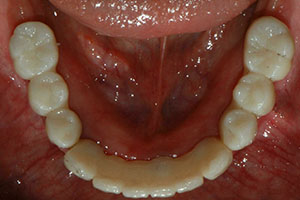

치료증례 전후사진

Before & After